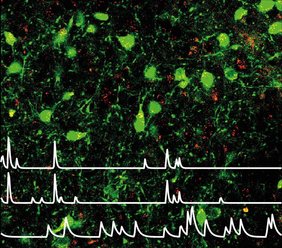

Die Forschenden nutzten Miniaturmikroskope, um die Aktivität einzelner Nervenzellen zu visualisieren, während die Mäuse verschiedene Umgebungen erkundeten und spontane Verhaltensweisen zeigten. „Wir haben die Aktivität Leptin-sensitiver Nervenzellen aufgezeichnet, während die Mäuse potentiell angstauslösenden Situationen ausgesetzt waren. Dabei haben wir gesehen, dass diese Nervenzellen immer dann aktiv wurden, wenn die Tiere sich trauten, von selbst in exponierte Bereiche einzutreten oder sich dort Nahrung näherten“, sagt Rebecca Figge-Schlensok, Doktorandin an der Universität zu Köln. „Als wir die Aktivität dieser Nervenzellen verstärkten, erkundeten die Mäuse mehr und konnten in herausfordernden Situationen fressen – klare Hinweise darauf, dass dieser Schaltkreis hilft, die Angst zu überwinden und adaptives, zielgerichtetes Verhalten zu unterstützen.“